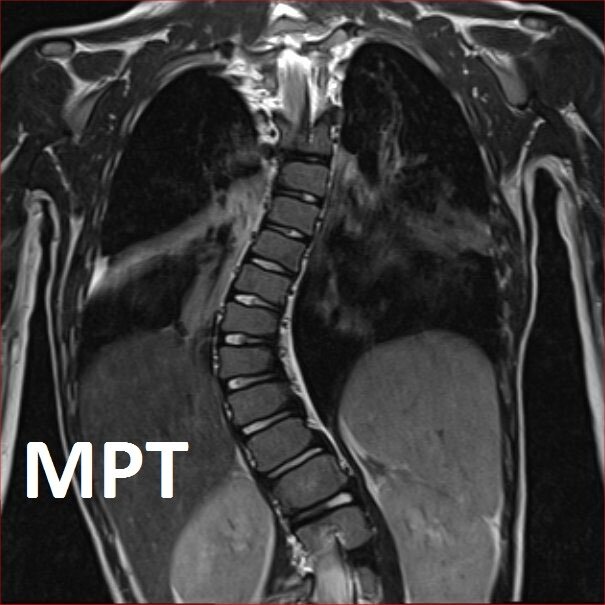

На МРТ не увидеть многих деталей, которые видны на рентгеновском снимке, т.к. принцип работы МРТ совершенно другой. Кажется, края позвонка четче, а на самом деле они не соответствуют действительности, не видно ротации и т.д.